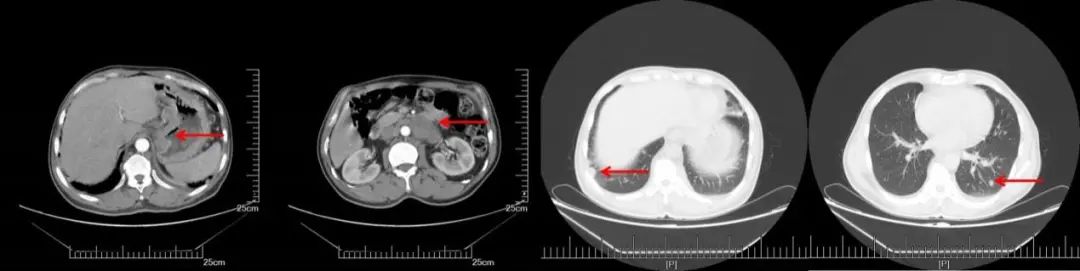

CT(2020.05.27):双肺多发转移瘤,较前大致相仿。双侧锁骨上、双侧膈肌脚后间隙、脊柱左旁、纵隔、腹腔、腹膜后及右侧髂血管旁等多发淋巴结,部分肿大,较前大致相仿。

A:CT增强(2018.11.07): 腹膜后多发淋巴结转移,部分较前增大。双侧锁骨上淋巴结转移,部分较前增大,双肺多发结节,转移可能;B:CT增强(2019.05.16):腹膜后淋巴结较前缩小,双肺转移较前增多增大;C:CT增强(2019.10.25):腹膜后淋巴结稳定,双肺转移较前增多增大;D:CT增强(2020.05.27):双肺转移瘤及腹腔淋巴结总体稳定。